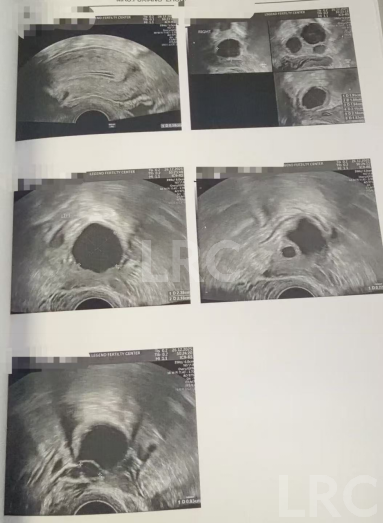

月经第二天 促排第一天

阴超检查:基础卵泡 4 颗

- 右侧卵泡 3 颗 (9,7,7,4mm)

- 左侧卵泡 1 颗 (9mm)

促排第五天

阴超检查(只数能用卵子):

- 右侧卵泡 3 颗 (14,12,11mm)

- 左侧卵泡 1 颗 (14mm)

促排第八天

阴超检查:

- 右侧卵泡 3 颗 (18,16,14mm)

- 左侧卵泡 1 颗 (18mm)

促排第九天

- 右侧卵泡 3 颗 (20,20,18mm)

- 左侧卵泡 2 颗 (23mm)

子宫内膜厚度:5..8mm